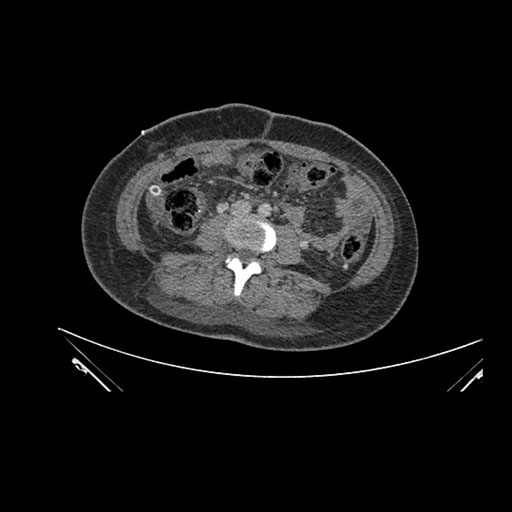

Imaging Analysis

Look through the patient's CT scan to identify any areas of concern for the necessary procedure.

Coronal Venous

Based on initial findings, which issue(s) would you be most concerned about?